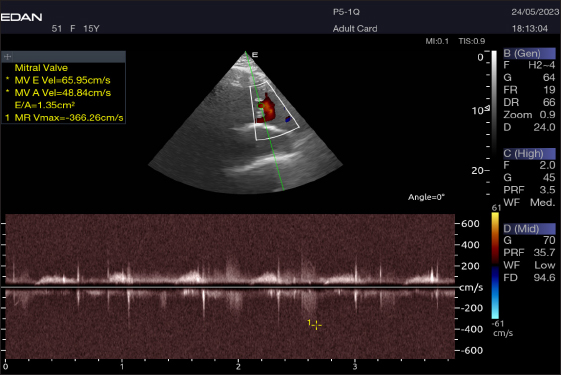

The Mv E/A (Fig. 8), Tv E/A (Fig. 9), and maximum velocity of the aortic valve (Av Vmax) (Fig. 10) were all measured using pulsed-wave Doppler at LPSLAx in all camels. Two cases were observed with mild mitral regurgitation detected through continuous-wave Doppler, but the regurgitation was not considered significant (Fig. 11).

Fig. 8. Left parasternal longitudinal axis of a 16-year-old racing camel showing pulsed wave Doppler over the mitral valve (1=E wave and 2=A wave).

Table 4 provides an overview of pulsed-wave Doppler echocardiographic serial measures in adult racing camels. The pulsed-wave Doppler echocardiographic measurements’ mean values ± standard deviation were recorded for Tv E/A (1.3 ± 0.2 cm2), Mv E/A (1.3 ± 0.2 cm2), Av max (−88.2 ± 25.1 cm/second), and Pv max (−59.2467 ± 17.4 cm/second), as shown in Table 4.

The pulsed-wave Doppler echocardiography of racing camels is not well documented. While all camels had their Mv E/A, Tv E/A, and maximum velocity of the Av Vmax recorded using pulsed-wave Doppler at (LPSLAx), the majority of cases (58.4%) had trouble measuring the pulmonary valve from the right short parasternal view. Using continuous-wave Doppler, minor mitral regurgitation was observed in two patients, but the regurgitation was not substantial.